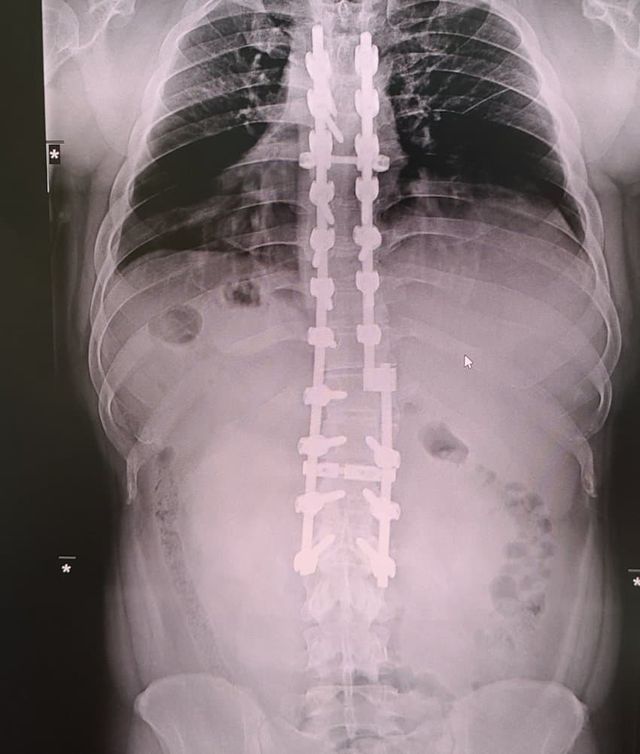

나 12사에서 죽을뻔하고 척추에 심 21개 박은 사람이다

[시리즈] 티타늄맨 이야기

나도 12사때 훈련병시절 완전 군장하고 쓰러지고

척추 무너지고 희귀병 진단받아서

12사 내 의무사단에서 핵고통 받다가 죽다살아난 사람이다

척추 심 21개

척추에 심 21개를 박는 것은 매우 심각한 의료적 조치입니다. 이는 대규모의 수술과 회복 과정을 필요로 하며, 환자의 삶에 큰 영향을 미칠 수 있습니다. 척추 수술이나 시술에 대한 정보와 경험을 나누는 것은 많은 사람들에게 유용한 자료가 됩니다.